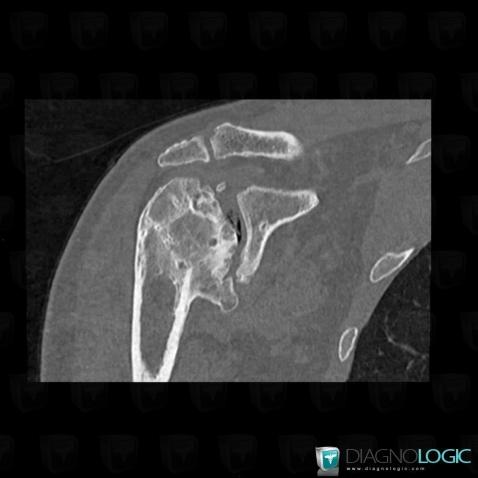

Degenerative joint disease, Scapula, CT

Here is the specific information in the key image above:

- Diagnosis Degenerative joint disease, Location(s) Scapula, with gamuts Epiphyseal osteolysis